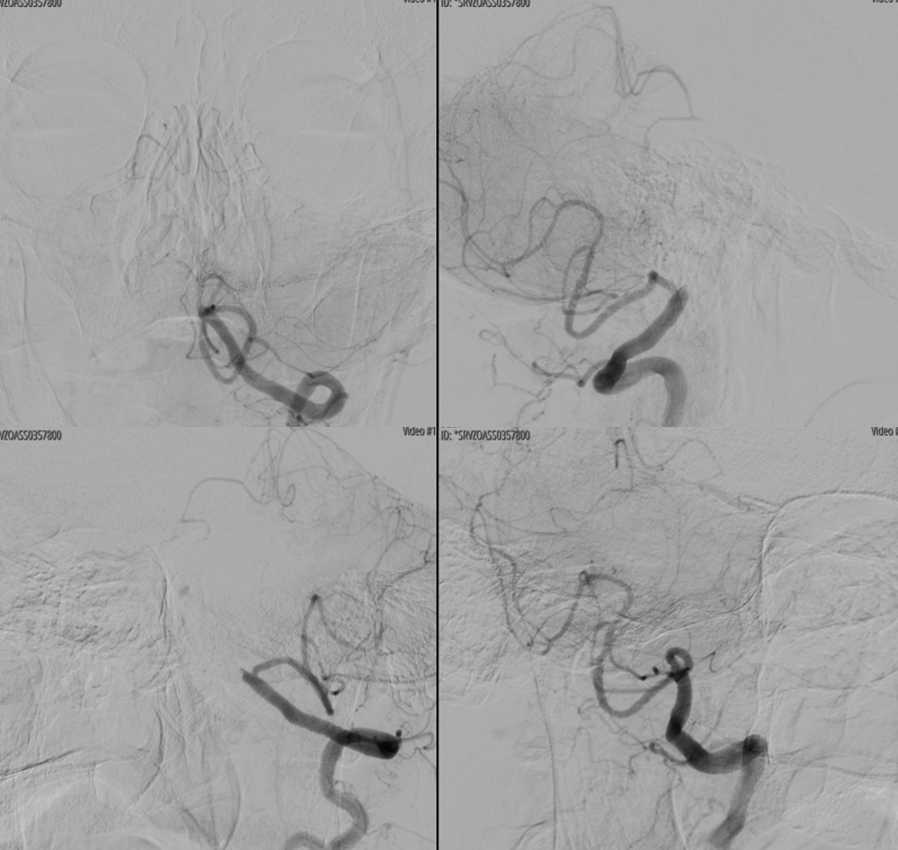

Stenting. Lots of calcs

“Dry” noncontrast Vaso-CT (22 cm FOV protocol, 20 seconds acquisition, reconstructed with 50% FOV and 5123 matrix), showing the stents in the artery and the calcific plaques.

Laser-cut balloon-mounted stents make it easier to leave the PICA alone – critical given what you see below. The best choice in our opinion.